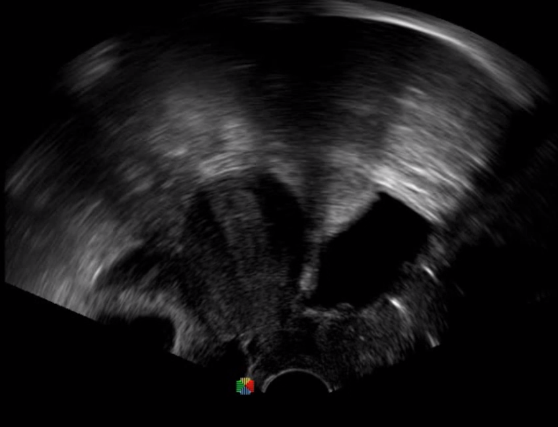

TEE(經(jīng)食道超聲心動圖)將超聲探頭置入食道內,從心臟的后方向前近距離探查其結構 ,克服了經(jīng)胸超聲檢查的局限性,避免肺內氣體、胸壁脂肪、胸廓畸形等因素影響,觀察角度更多,圖像更加清晰,測量數(shù)據(jù)更準確。

經(jīng)食道超聲 大動脈短軸